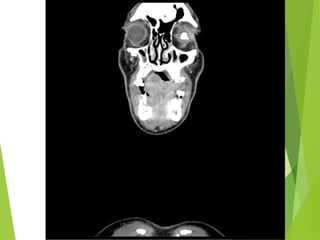

Estudios de imagen

20 de Marzo 2013

Estudios de Imagen:

-TAC de cuello simple y contrastado

20 de Marzo2013 Estudios de Imagen: -TAC de cuello simple y contrastado